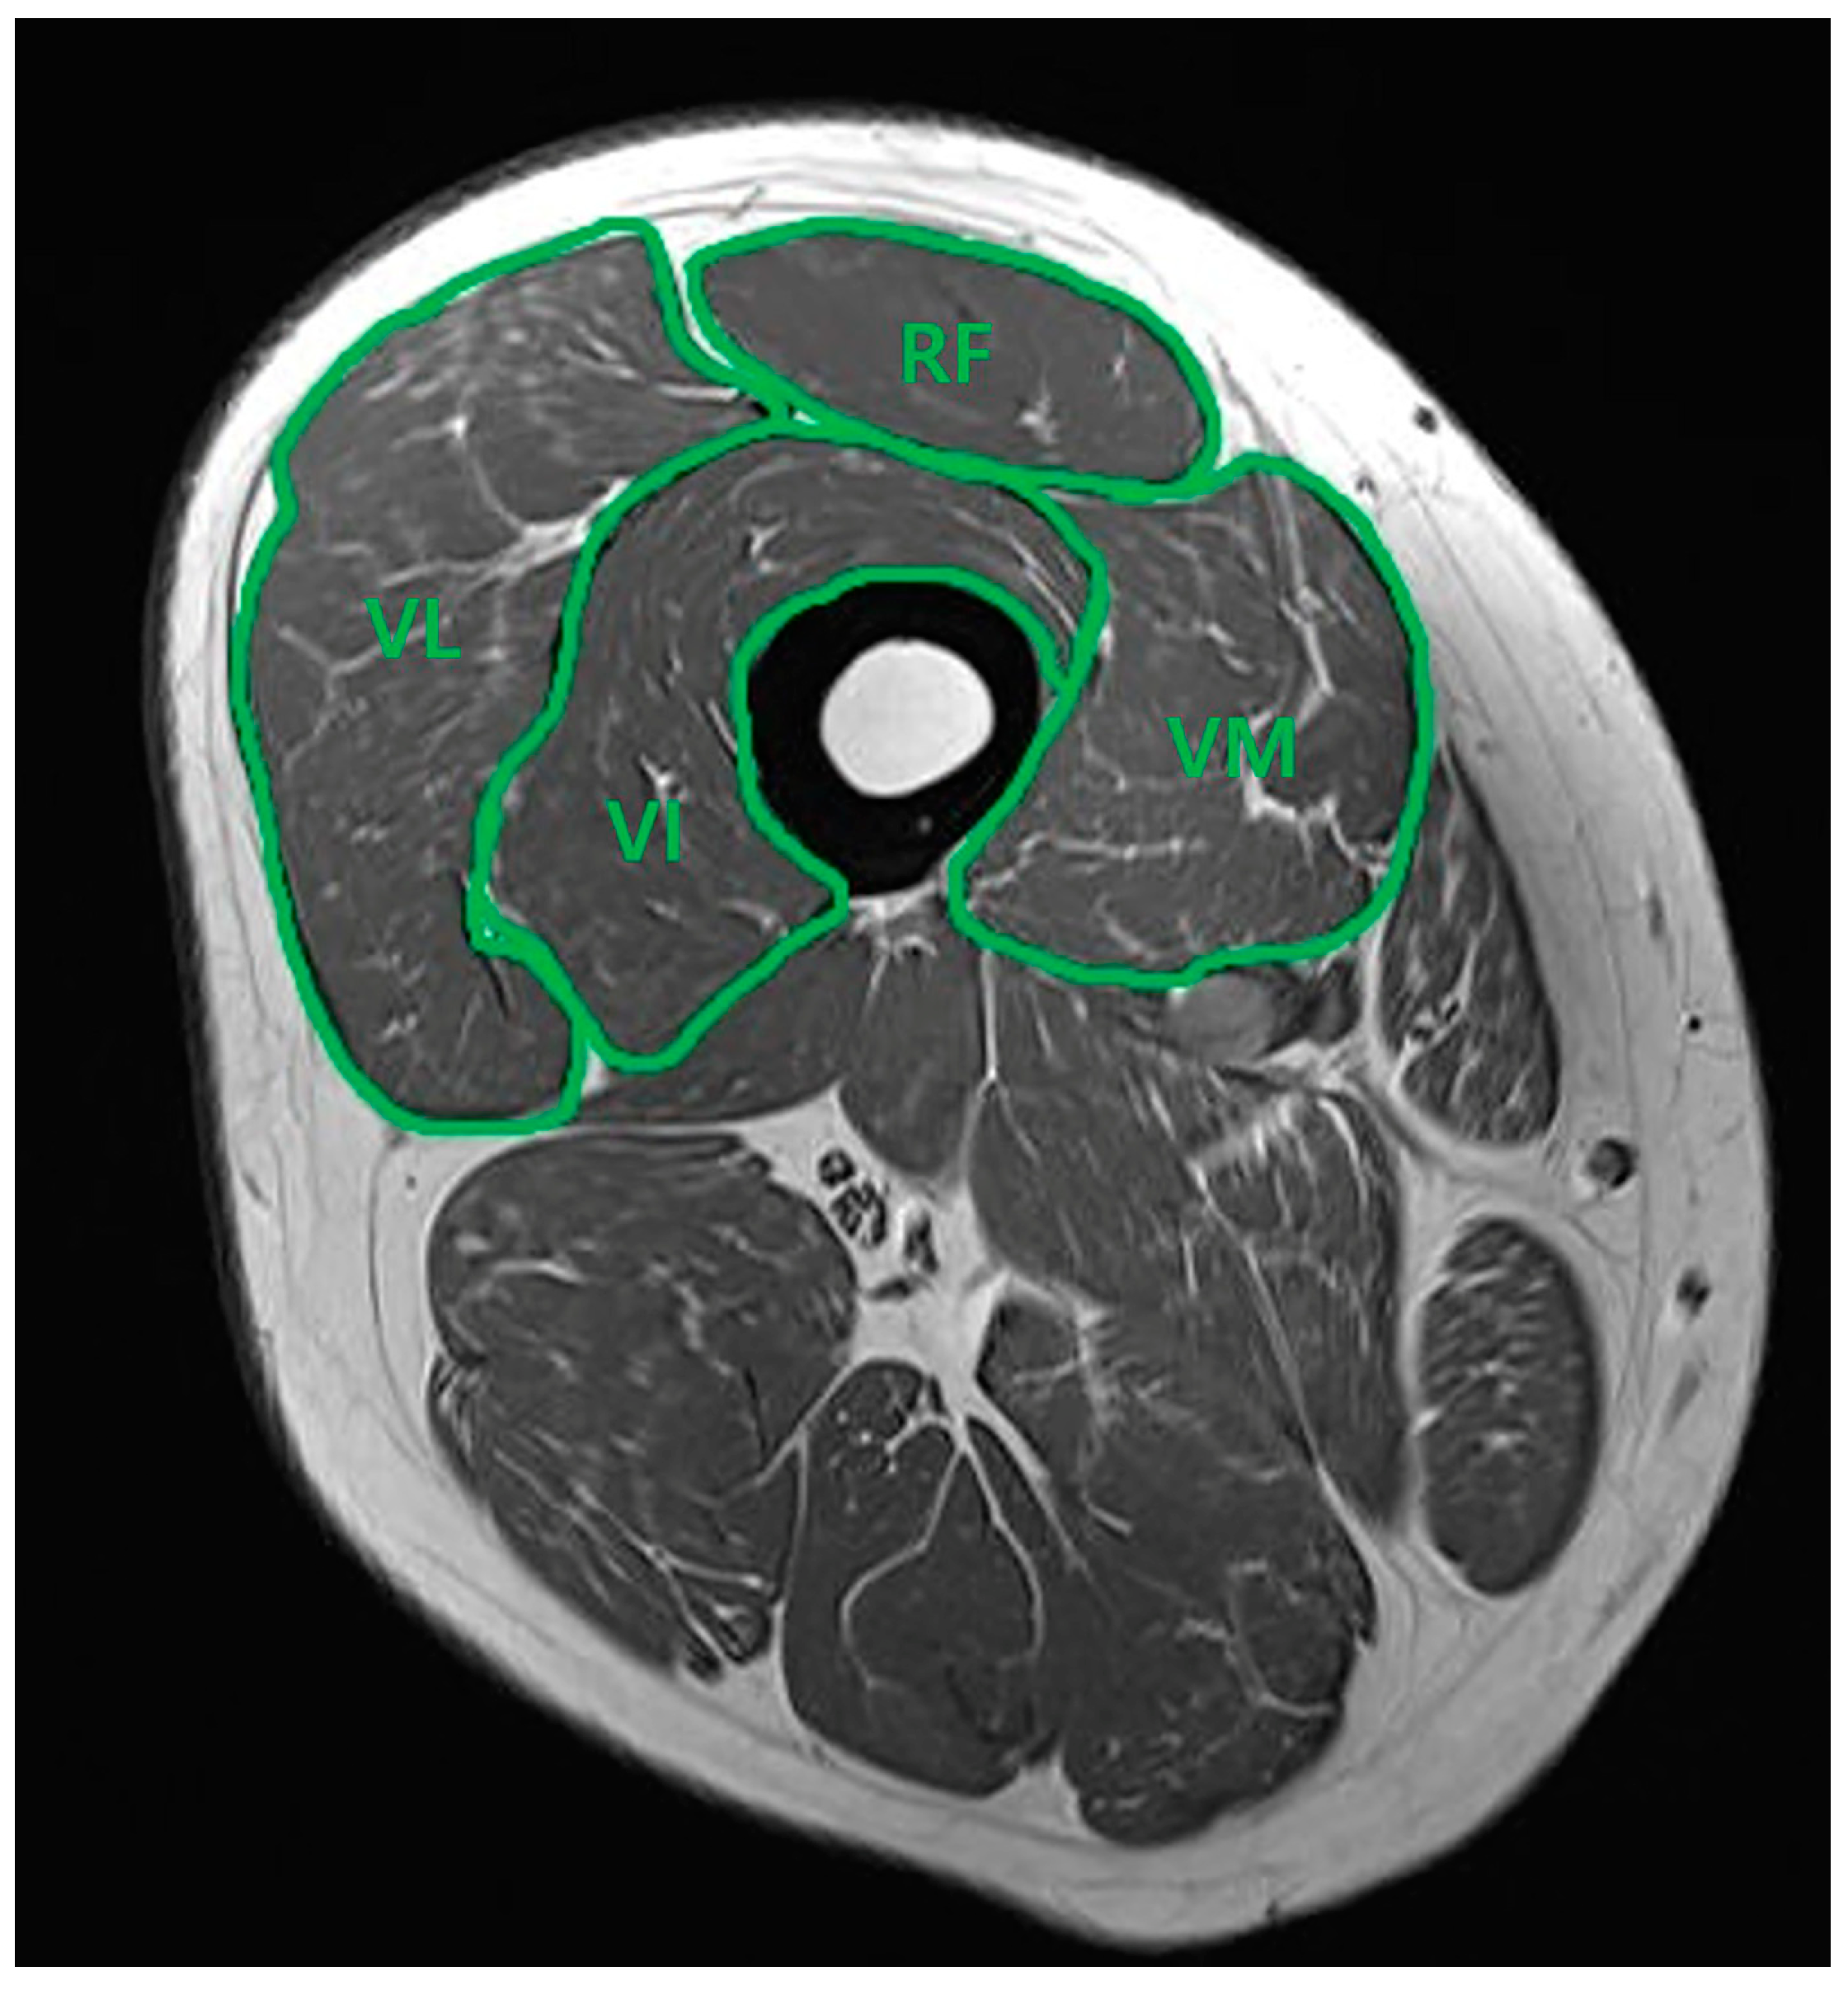

A consecutive series of MRI scans of each patient’s thighs was acquired using a 1.5T MRI system (Siemens Magnetom Avanto System; Siemens Medical, Erlangen, Germany). Close collaboration with the radiology department was maintained throughout the study to ensure precise measurements. Oblique sagittal T2 TSE MRI scans, perpendicular to the long axis of the scapular body, were obtained with a slice thickness of 3 mm. The contours of the rectus femoris (RF), vastus intermedius (VI), vastus medialis (VM), and vastus lateralis (VL) muscles were manually traced using PACS software (Picture Archiving and Communication System, DICOM version 3.0 INFINITT, Infinitt Healthcare, Seoul, Republic of Korea). As illustrated in Figure 1, the borders of the four muscle groups were delineated in the mid-thigh view on the axial plane. The software then automatically calculated the cross-sectional area (CSA) for each muscle. Subsequently, the percentage of each muscle relative to the total quadriceps muscles (rCSA) was determined. Two knee-specializing orthopedic surgeons, who worked in the territory university hospital (*** and ***), independently performed the image measurements. Interobserver reliability was reassessed through a randomized analysis conducted three months later.

Figure 1.

Axial T2 TSE MRI. Measurement of the cross-sectional area of the quadriceps muscle in mid-thigh view. Rectus femoris (RF), vastus intermedius (VI), vastus medialis (VM), and vastus lateralis (VL).